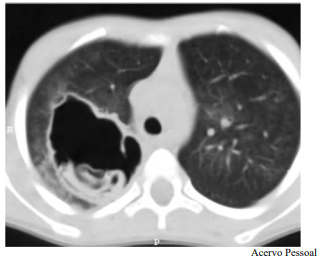

Determinado paciente de 49 anos de idade, morador em zona rural, iniciou com quadro de tosse importante, com piora progressiva, de início há dois meses, associada a alguns episódios de vômica. Refere febrículas na última semana. O paciente é tabagista leve, trabalha com criação de ovelhas e mora em casa com cachorros e gatos. Nega viagens internacionais recentes. Não foi encontrada nenhuma alteração no exame físico. Verificaram-se FC = 80 bpm, FR = 20 irpm e SatO2 = 99% em ar ambiente. A tomografia de tórax apresenta uma lesão cística de paredes espessas e conteúdo heterogêneo em seu interior, conforme representado na imagem a seguir.

Tendo em vista esse caso clínico e os conhecimentos médicos correlatos, julgue o item a seguir.

Esse paciente tem indicação de remoção cirúrgica da lesão.